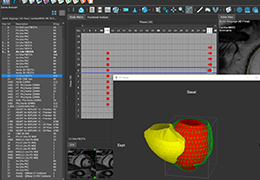

View X-Ray CT & MRI Scans Fast and Easily

Designed for surgeons, Pro Surgical 3D makes it easy to view patient scans quickly. Pro Surgical 3D facilitates the optimal 3D treatment and assessment workflows based on X-ray CT and MRI scans – and best of all, it’s FREE!

High-quality and fast 3D reconstruction and 3D rendering

Performs 3D reconstruction and volume rendering.

Instant and interactive surface extraction and export to STL and PLY formats.